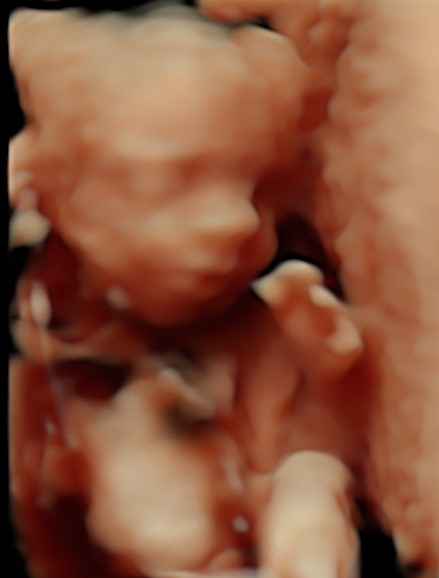

4D/5D/HD Ultrasound Gallery

Gallery